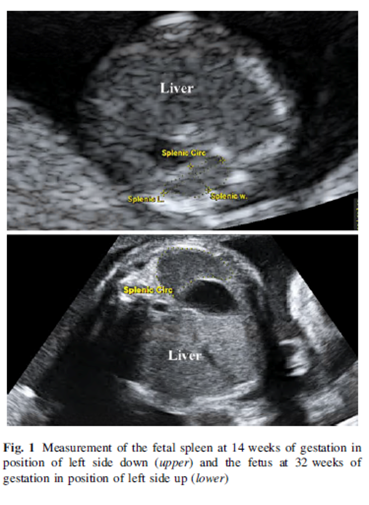

Srisupundit K et al., Reference range of fetal splenic circumference from 14 to 40 weeks of gestation, Arch Gynecol Obstet.2011 Mar;283(3):449 - 453

Beispiel Milzumfang

Tabelle Milzumfang